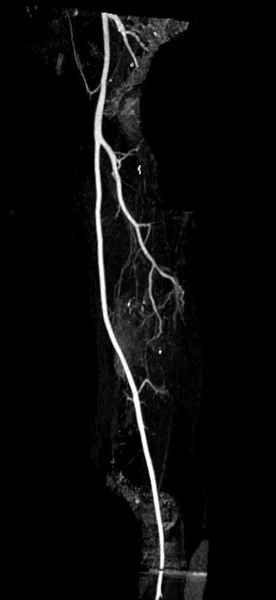

Для предупреждения кровотечения во время рассверливания, за день до операции провели эмболизацию сосудов питающий метастаз. http://radiology.rsnajnls.org/cgi/reprint/150/3/673.pdf (7-11, 12-15-16)